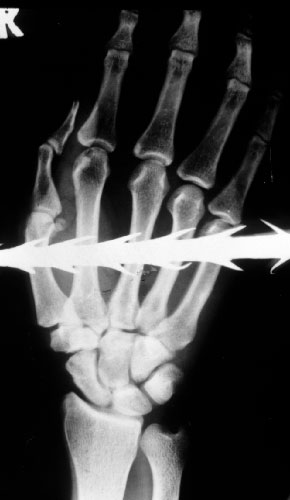

Zimbabwe A spear shot through a man’s hand. Photograph: Courtesy Hermann Vogel